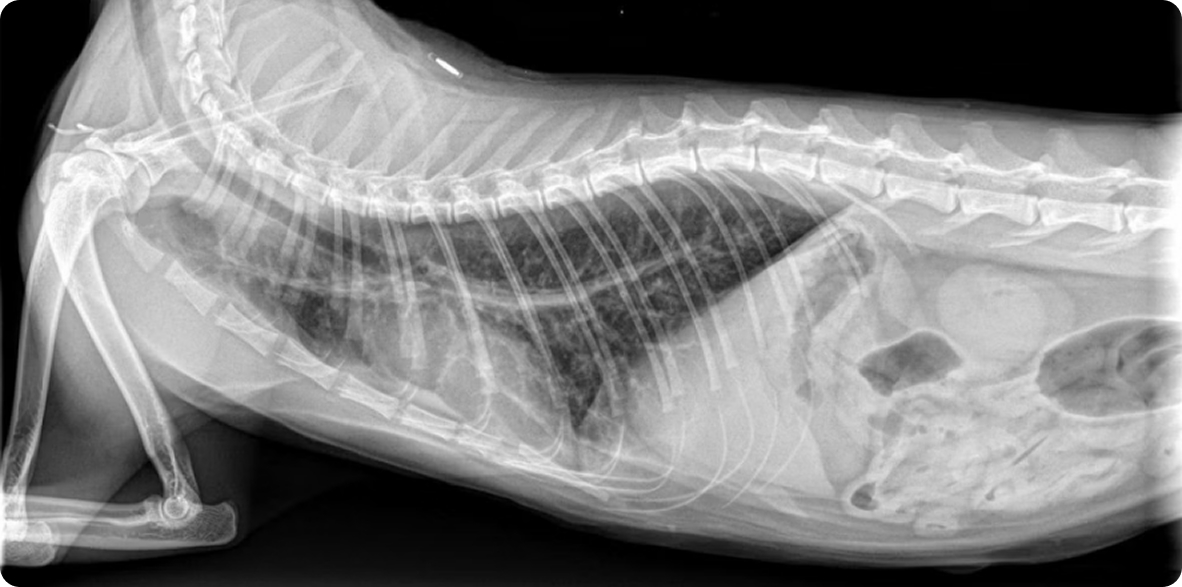

Рентгенография грудной клетки |

Позволяет оценить состояние бронхов и легочной ткани. При бронхопневмонии видны участки затемнения альвеолярного и интерстициального типа. Особенно информативно у щенков при подозрении на осложнения. |